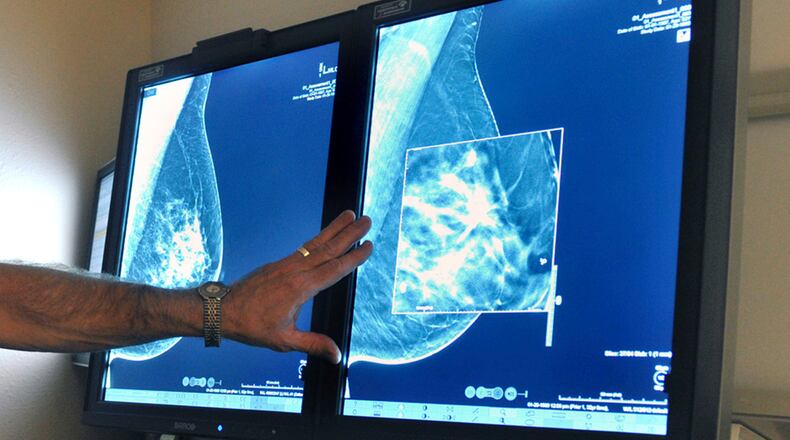

“Early detection of breast cancer also makes a big difference when women practice breast self-examination and schedule regular mammograms. The earlier breast cancer is found, the more likely it will be survivable.”

Follow your doctor’s advice on when and how often to get a mammogram. Premier Health and the National Comprehensive Cancer Network recommend a mammogram every year beginning at age 40 for women at average risk. No physician referral is needed for a screening mammogram.